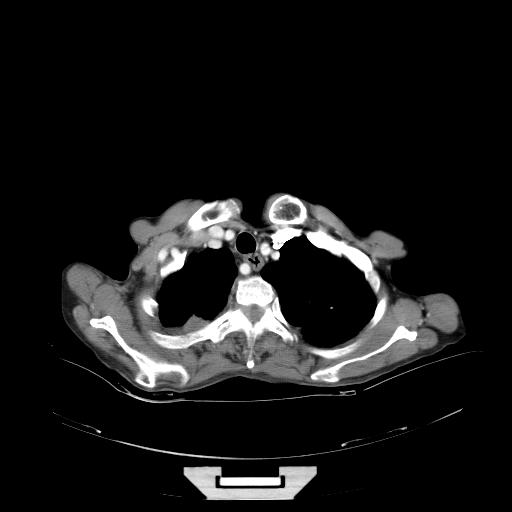

女,72岁,咳嗽一周余,突发右下肢无力二天。

pe:bp-140、80mmhg,精神可,伸舌居中,右上肢肌力正常,右下肢肌力0级,巴氏征+

来院做头颅+胸部ct平扫

遂加作增强:

胸部病变平扫35hu,增强强化至70hu

这个病人首先是胸部病变的定位到底是肺内还是肺外。仔细观察块影位于胸膜下,与胸膜间有透亮带,且近端血管未见明显推移而是引流样改变,形态分叶,说明这个病灶位于肺内胸膜下。很可能是腺癌,腺癌最易致颅内高密度转移灶。局部胸膜有侵犯。

本例颅内见多发大小不等高密度灶,有强化及水肿;另外,胸锁关节层面可能是第四胸椎及右侧肋骨起始部骨质欠连续,椎旁软组织肿胀,建议调骨窗观察。

诊断:右下肺癌伴颅内、胸椎、肋骨转移可能性最大。